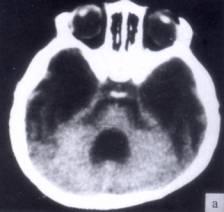

问题 病历摘要:??患者女性,10岁。结核性脑膜炎愈后8月,头痛伴恶心呕吐1周,并渐加重。体检:神清,精神差,反应迟钝,双眼底视神经乳头水肿,双眼外展差,余未见明显异常。 该患者宜采用下列哪种治疗手段?

选项 A.侧脑室-枕大池分流术 B.终板造瘘术 C.侧脑室-腹腔分流术 D.侧脑室-右心房分流术 E.侧脑室-颈静脉分流术 F.腰椎蛛网膜下腔-腹腔分流术 G.脉络丛烧灼术

答案 C